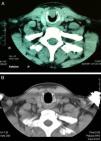

Se describe el caso de un varón de 50años que consultó por disnea progresiva durante 3meses a medianos y grandes esfuerzos con estridor inspiratorio leve. Destacaba el antecedente de intubación previa por 2 cirugías de clavícula 2años antes. La rinofibrolaringoscopia en consulta mostró una lesión subglótica anterior derecha y la tomografía computarizada (TC) determinó su extensión (fig. 1A). Se programó broncoscopia rígida y resección láser (neodimio-YAG) y durante la cirugía se realizaron tomas biópsicas y vaporización parcial de la lesión. El resultado anatomopatológico fue compatible con un adenoma pleomorfo, por lo que, en un segundo tiempo, se realizó una resección subglótica mediante abordaje externo: exposición de la tráquea con incisión sobre el segundo anillo similar a la utilizada para una traqueotomía; incisión de la membrana cricotiroidea; unión vertical de ambas incisiones en su porción lateral izquierda (sección de arco cricoideo y anillo traqueal), levantando una charnela para visualizar directamente la lesión (de 15mm de diámetro, situada a lo largo de la cara interna de arco cricoideo hasta la altura del borde superior del primer anillo traqueal). Se completó la exéresis con resección cricotraqueal parcial (arco cricoideo y porción anterior de primer anillo traqueal). El defecto se cerró mediante reconstrucción primaria con plastia muscular (esternotiroideo) sobre tubo de silicona en T de Montgomery (8mm) y cierre por planos. El paciente fue dado de alta a los 5días con un enfisema subcutáneo cervical de grado leve-moderado que persistió 5semanas, odinofagia que precisó dieta blanda durante un mes, y disfonía por la situación del borde superior del stent sobre las cuerdas vocales. El estudio anatomopatológico definitivo fue de tumor benigno de glándula salival, compatible con adenoma de células basales (adenoma monomorfo), con márgenes libres. El stent en T se retiró a los 4meses y se evidenciaron granulomas vocales que desaparecieron en 2semanas con prednisona oral (30mg en pauta descendente), normalizándose la voz. Durante el último año y medio se ha realizado seguimiento periódico del caso mediante rinofibrolaringoscopia y controles radiológicos (fig. 1B), sin evidencia de recidiva hasta la fecha.